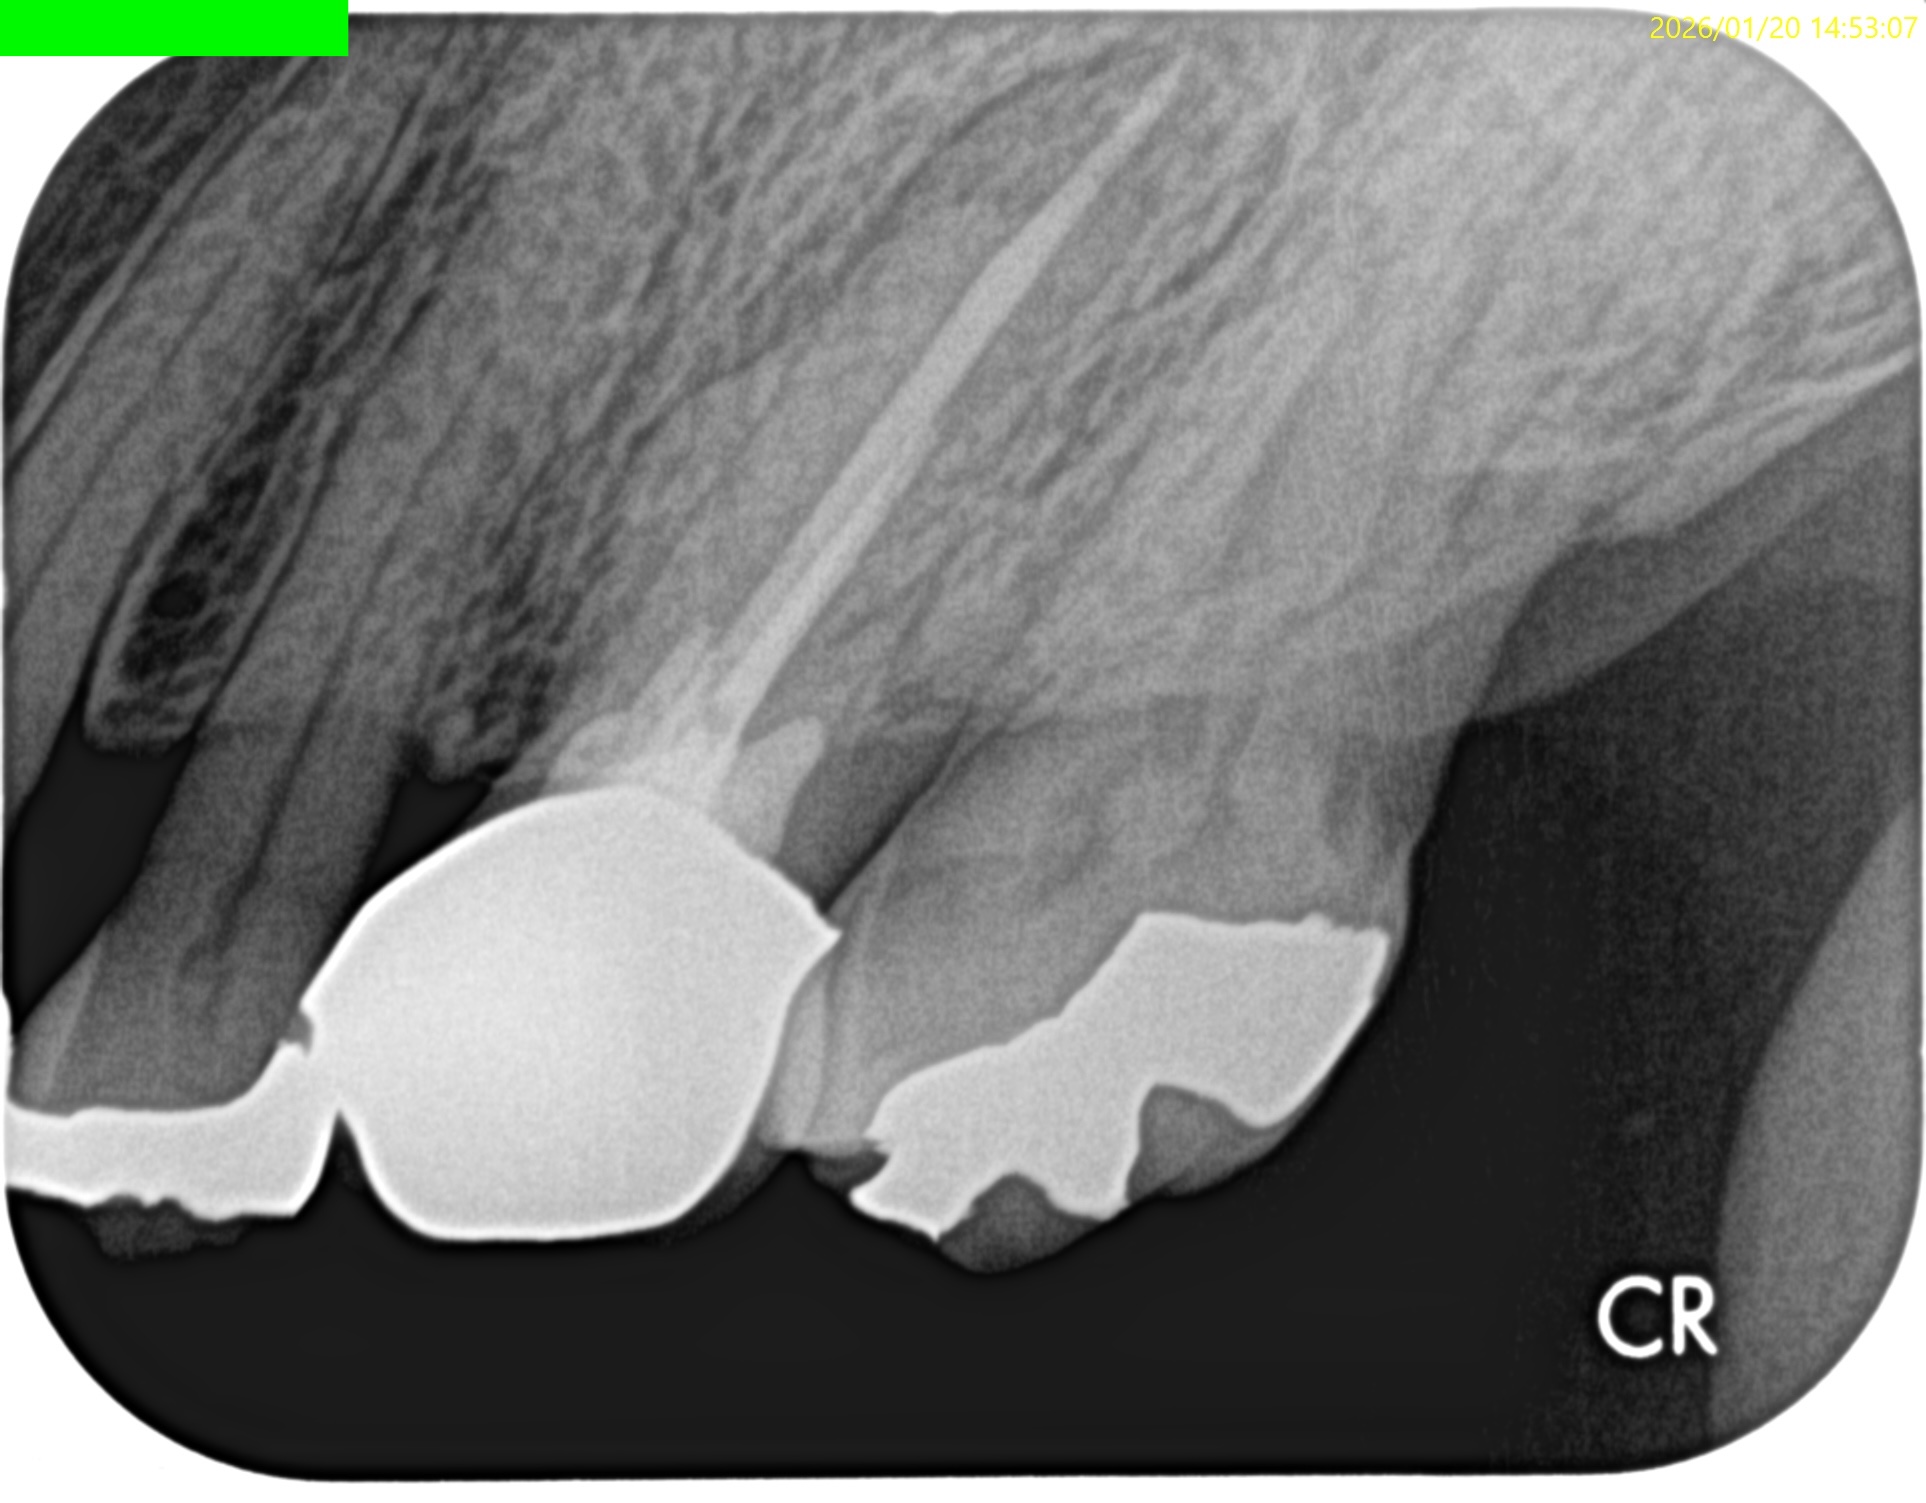

ということで治療時に以下のように修正した。

術後にPA, CBCTを撮影した。

問題はないだろう。